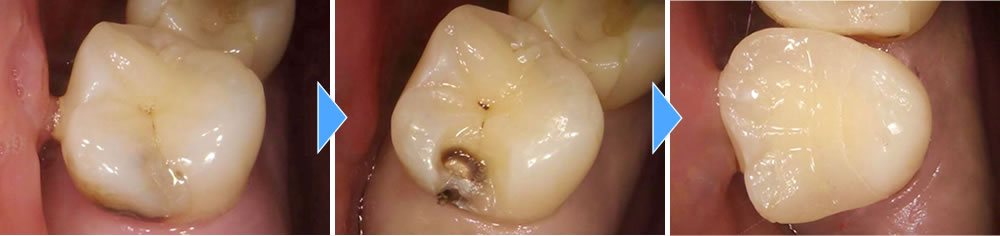

歯の内部まで進行した虫歯を除去しセラミックインレーで治療した症例

年齢

20代

性別

女性